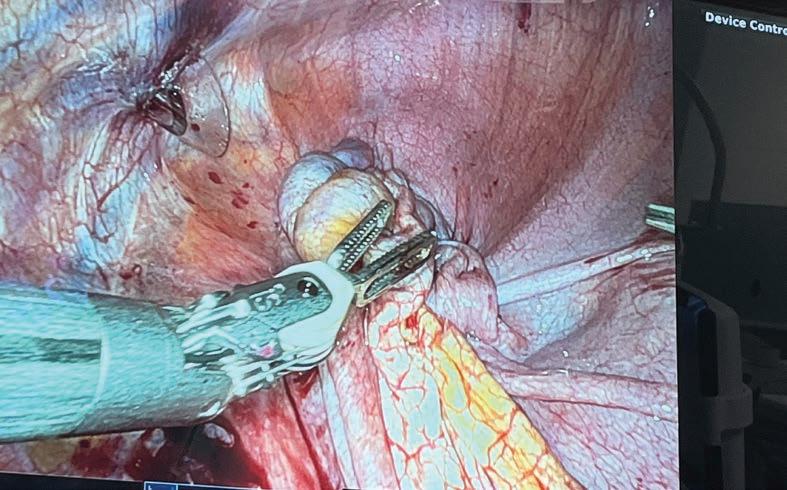

Urologist and prostate cancer surgeon Dr Tom Shannon aims to be in his patient’s lives for the shortest time possible.

“I love the fact that I can be important to a patient for a very short period of time. The goal is not to need me and to get on with their lives, free of cancer, which is such a privilege to be part of. Our team makes a difference,” he says.

Tom has been a urologist for more than 25 years, specialising in prostate cancer diagnosis and treatment. He still loves his profession as much today, if not more than when he started.

A/Prof Shannon is a graduate of the University of WA. He completed his Fellowship in Urology in 1999 and completed post-fellowship training in the UK and the US focusing on minimally invasive surgery and prostate brachytherapy. He was a pioneer of minimally invasive urological surgery in WA and is a leader in the development of prostate MRI. He is a strong advocate for men’s health and has been a board member of the Prostate Cancer Foundation of Australia (WA) for over 10 years.

Among other accomplishments, in 2004 Tom operated in WA with the pioneering French surgeon Professor Claude Abbou for the first demonstration of a laparoscopic radical prostatectomy. To date, the urologist has cared for more than 10,000 men and performed more than 3,000 open, laparoscopic and robotic surgeries.

“The goal is to find significant cancers early and cure them. Cures are achieved by complete surgical resection, which is a challenge, because you get one chance to do it really well. There are minimal margins for the cancer. To cure and retain continence and sexual function, you must be precise. The trifecta is the goal. Cure avoids needing testosterone suppression, which can be devastating.”